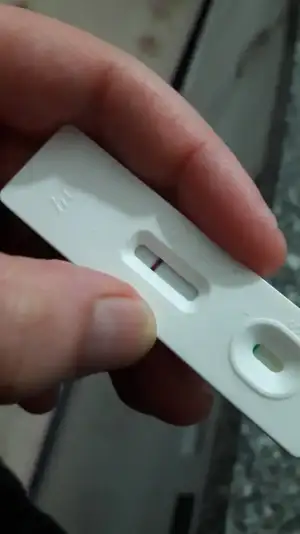

kizlarr ❤ benim bugun 14. gunum :) Normalde test yapmicaktim adetimi beklicektim ama 2 gundur vajinam ve kasigima ara ara agri vuruyor cok hafif 1 dk suruyor geciyor. dayanamadim aldim dedim yani varsa var yoksa bir dahaki aya. 2 3 saat once yaptim yani akşam idrarıyla :) ilk 3 dakikada gozle gorulebilir kirmizi cizgi cikti. İnanamadım, dedim idrar kurumuştur. Su damlattım gitmedi orda öyle hala 2. cizgi :) sizce varmi gebelik, sabah ilk işim kan vermek